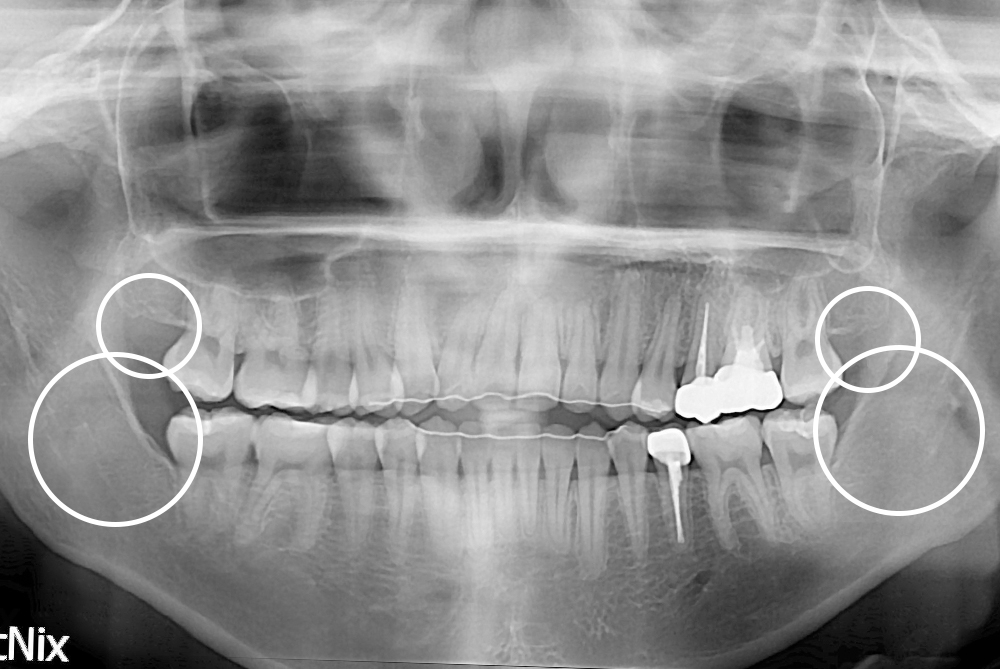

[사랑니] 매복 사랑니 발치

치료후 : 2021-04-07

세종치과는 구강악안면외과학 박사이신 원장님이 발치하는 치과입니다.